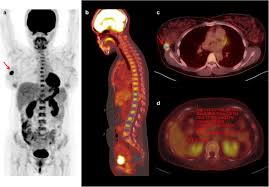

여기에 방사성 핵종 F-18를 붙여(F-18 FDG라고 함) 혈관 주사하면 빨리 자리는 암세포는 포도당이 더 필요해 정상 세포보다 10∼100배 더 많이 모여들고 이를 방사능으로 촬영해 찾아낸다. 암이 1㎝만 돼도 10조개의 암세포가 있어 CT, MRI 소견이 애매한 경우 유용하게 쓰인다.

물론 PET도 아주 작은 암은 놓치기도 하지만 대체로 약 0.5㎝ 이상의 암은 거의 80% 찾아내고 있다고 한다.

또 부수적으로 뇌 부분의 PET 영상으로 분석해 뇌졸중, 알츠하이머 치매도 조기 진단할 수 있다고 한다. 검사도 간단해서 정맥 주사를 맞고 1시간대기 후에 20분 정도 누운 상태로 촬영한다.

마지막으로 말씀드릴 점은 모든 초기 암을 PET 검진으로 해결할 수는 없다. 가령 위벽에 붙어 있는 0.5 cm 이하의 암이 포도당 대사마저 느리다면 알 수가 없기 때문이라고 한다.